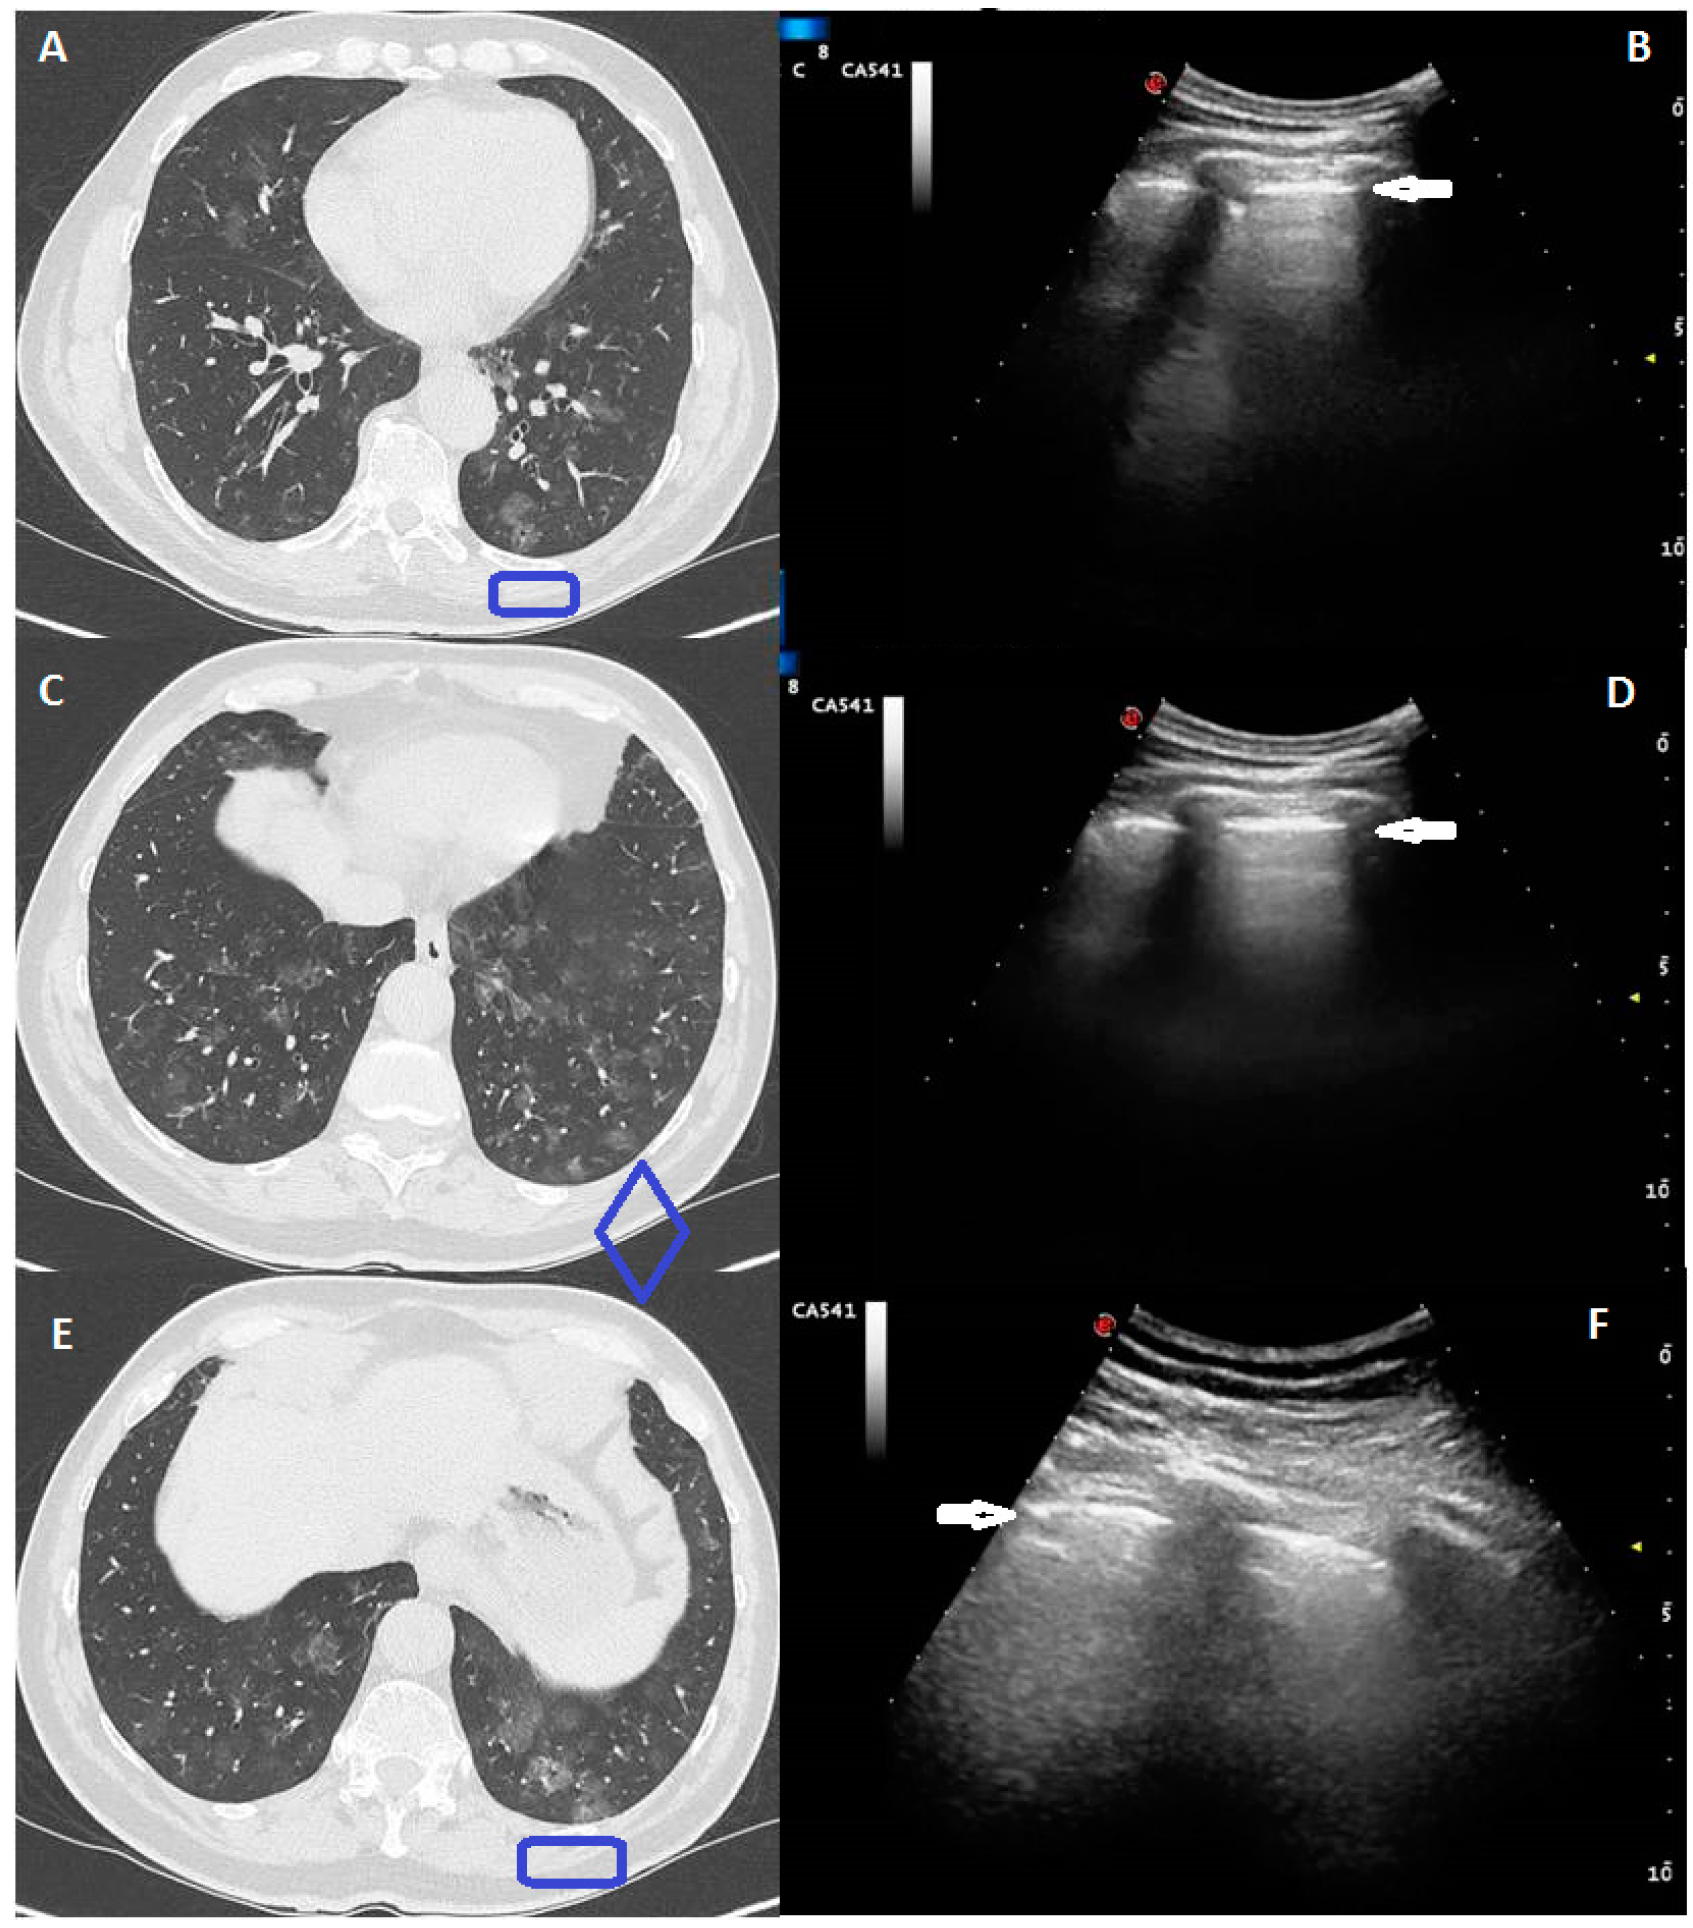

- The Chest-CT crazy pattern of bilateral, patchy, or extensive peripheral GGOs associated with smooth interlobular and intralobular septal thickening was identified at LUS in a total 30/58 patients (52%), with an echographic pattern consisting in a blurred and thickened hyperechoic pleural line, with or without associated subpleural hypoechoic lung striae, and B-lines below the pleural line (Figure 1).